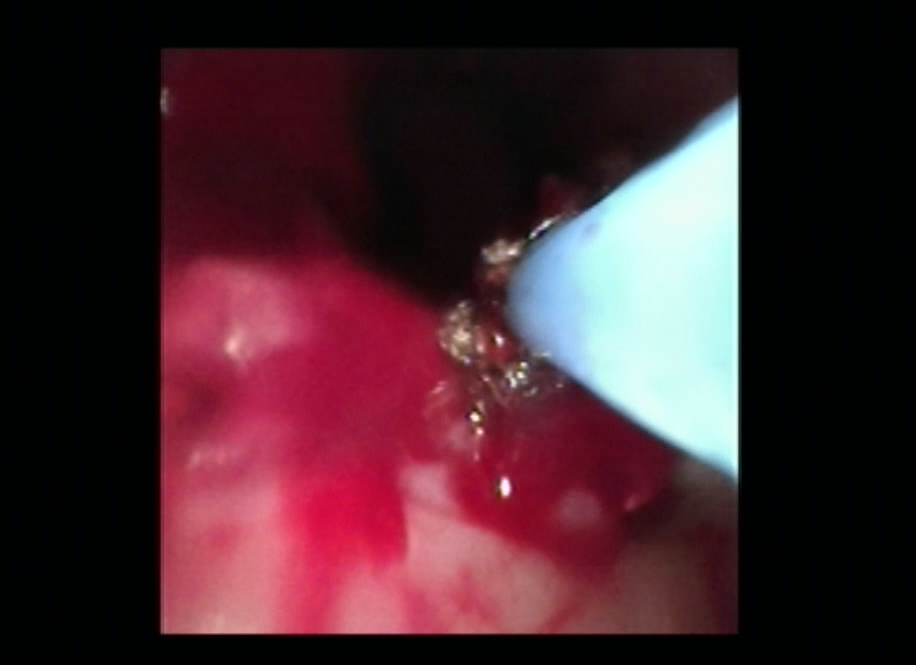

手术中,胸外科团队采用多技术联合操作策略:首先通过常规电子支气管镜完成病变探查与定位,随后置入硬支气管镜建立稳定操作通道,保障术中通气安全。针对气道内增生组织,团队交替使用氩气刀进行精准切除,并应用冷冻治疗仪对残余病灶进行消融与止血。最后在硬镜支撑与细支气管镜引导下,完整取出原有气管支架,未对气道黏膜造成附加损伤。

▲术中氩气刀治疗